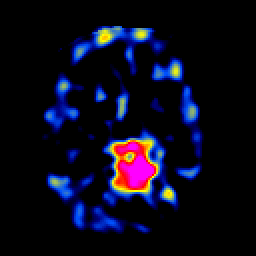

SPECT TL Study #5 -- Slice #35

[Home][Help][Clinical][Tour 1][Tour 2][Tour 3] Slice 35